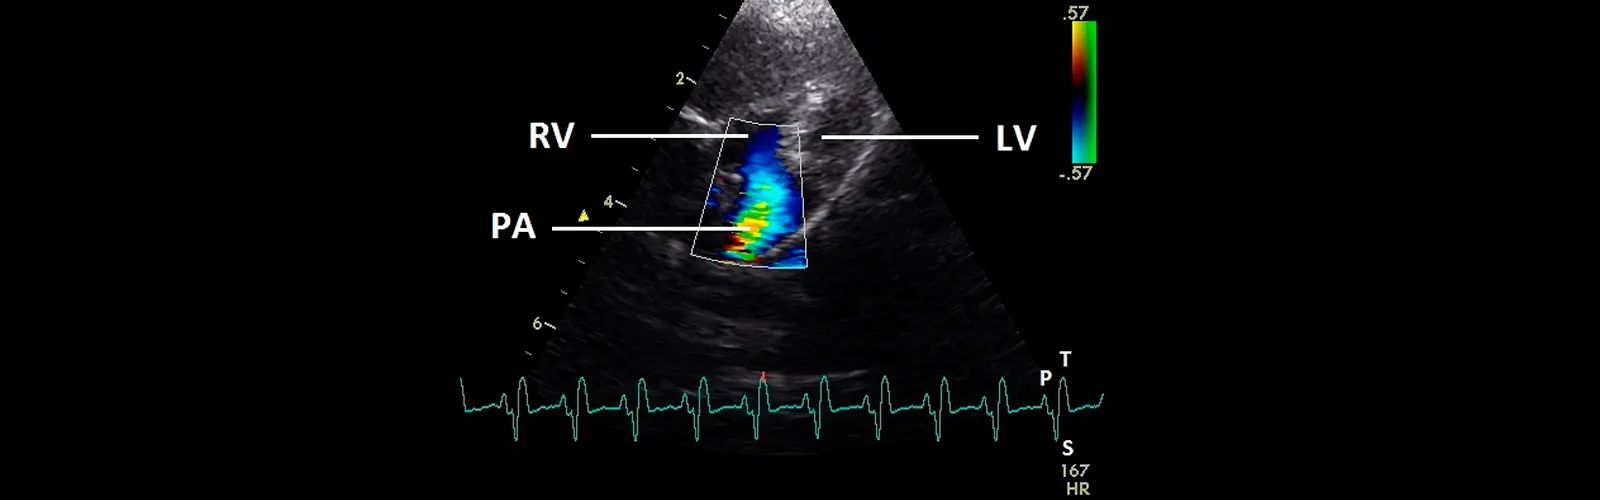

Diagnosis of valvular heart disease: Valvular heart disease occurs when one or more of the heart valves do not function properly. Color Doppler can help identify the type and severity of valvular heart disease by assessing the flow of blood across the valves.

Evaluation of heart function: Color Doppler can provide information about the direction and velocity of blood flow through the heart, which can help assess heart function and identify any abnormalities.

Diagnosis of congenital heart defects: Color Doppler can be used to diagnose and monitor congenital heart defects, which are structural abnormalities present at birth. The technique can provide detailed information about blood flow patterns in the heart and blood vessels, allowing for accurate diagnosis and monitoring.